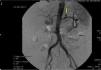

Con todos los hallazgos reseñados se decidió realizar una tomografía axial computarizada (TAC) con contraste en la que se informaba la presencia de un nódulo hiperdenso en la región posterior del fundus gástrico compatible con seudoaneurisma de la arteria gástrica izquierda, con un hematoma subyacente (fig. 1). Se realizó embolización percutánea transcatéter del seudoaneurisma con el uso de coils, presentando buen control angiográfico (fig. 2).